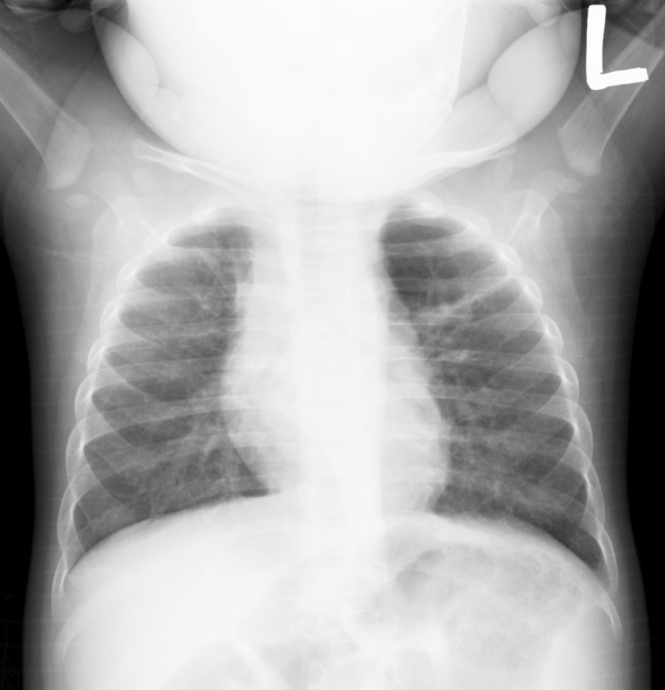

A Case of Asymptomatic Juvenile Emphysema.